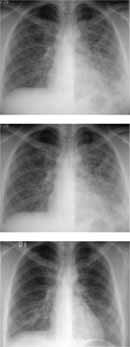

Figura 7. Radiografía de tórax tomada al ingreso, en comparación con la realizada dos días después, donde se observan densidades neumónicas diseminadas, más confluentes en la periferia.

El día del ingreso se inició manejo con Moxifloxacino y Tetraciclina por el antecedente de exposición a aves. Se realizó una tomografía de tórax de alta resolución.

Figura 8. Tomografía de tírax de alta resolución que muestra lesión intra alveolar predominante en la periferia de todos los lóbuos pulmonares y engrosamiento intestinal.

Se tomó radiografía de tórax al ingreso que mostró imágenes difusas compatibles con ocupación alveolar (Ver Figura Nº 10)

Figura 10. Se observa en la primera radiografía extensas áreas de ocupación alveolar que comprometen predominantemente el hemitórax izquierdo y zona central del hemitórax derecho, hallazgos asimétricos que van desapareciendo en la progresión del tiempo.